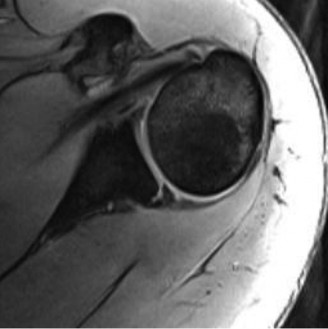

A 24-year-old, male athlete sustains an anterior shoulder dislocation. His MRI is shown in Figure 2–32.

Figure 2–32

The correct answer is (A). The MRI demonstrates an HAGL lesion. The MR arthrogram shows fluid extending down the medial humerus and is indicative of an HAGL. Most commonly, with an anterior dislocation, the anterior band of the inferior glenohumeral ligament is torn. With a posterior dislocation, the posterior band is torn creating a reverse HAGL. The ligament tends to tear off the humeral side. These are important injuries to identify as arthroscopic labral repair and capsular shift may be unsuccessful without concomitant repair of the HAGL lesion. Many authors advocate an open approach to repair an HAGL lesion.